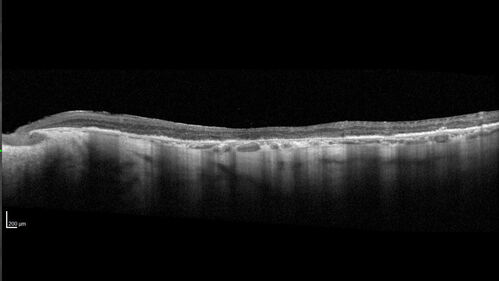

Optic Disc Melanocytoma - Atypical

45 year old female with normal vision and optic nerve lesion in the left eye. VA 20/16 OU. Extensive testing was normal including brain and orbit MRI. The lesion has been stable for 5 years.

AMD End stage both eyes - scar OD - GA OS